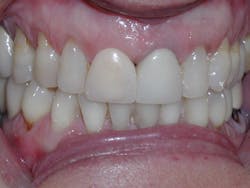

The six-week follow-up visits with Evin were eye-opening! I had the opportunity to observe his periodontal condition improve at each interval. After 30 aligners, or 15 short months, Evin's clear aligner orthodontic treatment was completed and final photos were taken. His bite was checked to confirm we had achieved our initial goal. Evin now had the appropriate overbite, overjet, and class I occlusion with proper posterior intercuspation with no interferences.

Figure 1

Compare the inclination of the long axis of teeth on #12 before and after treatment.